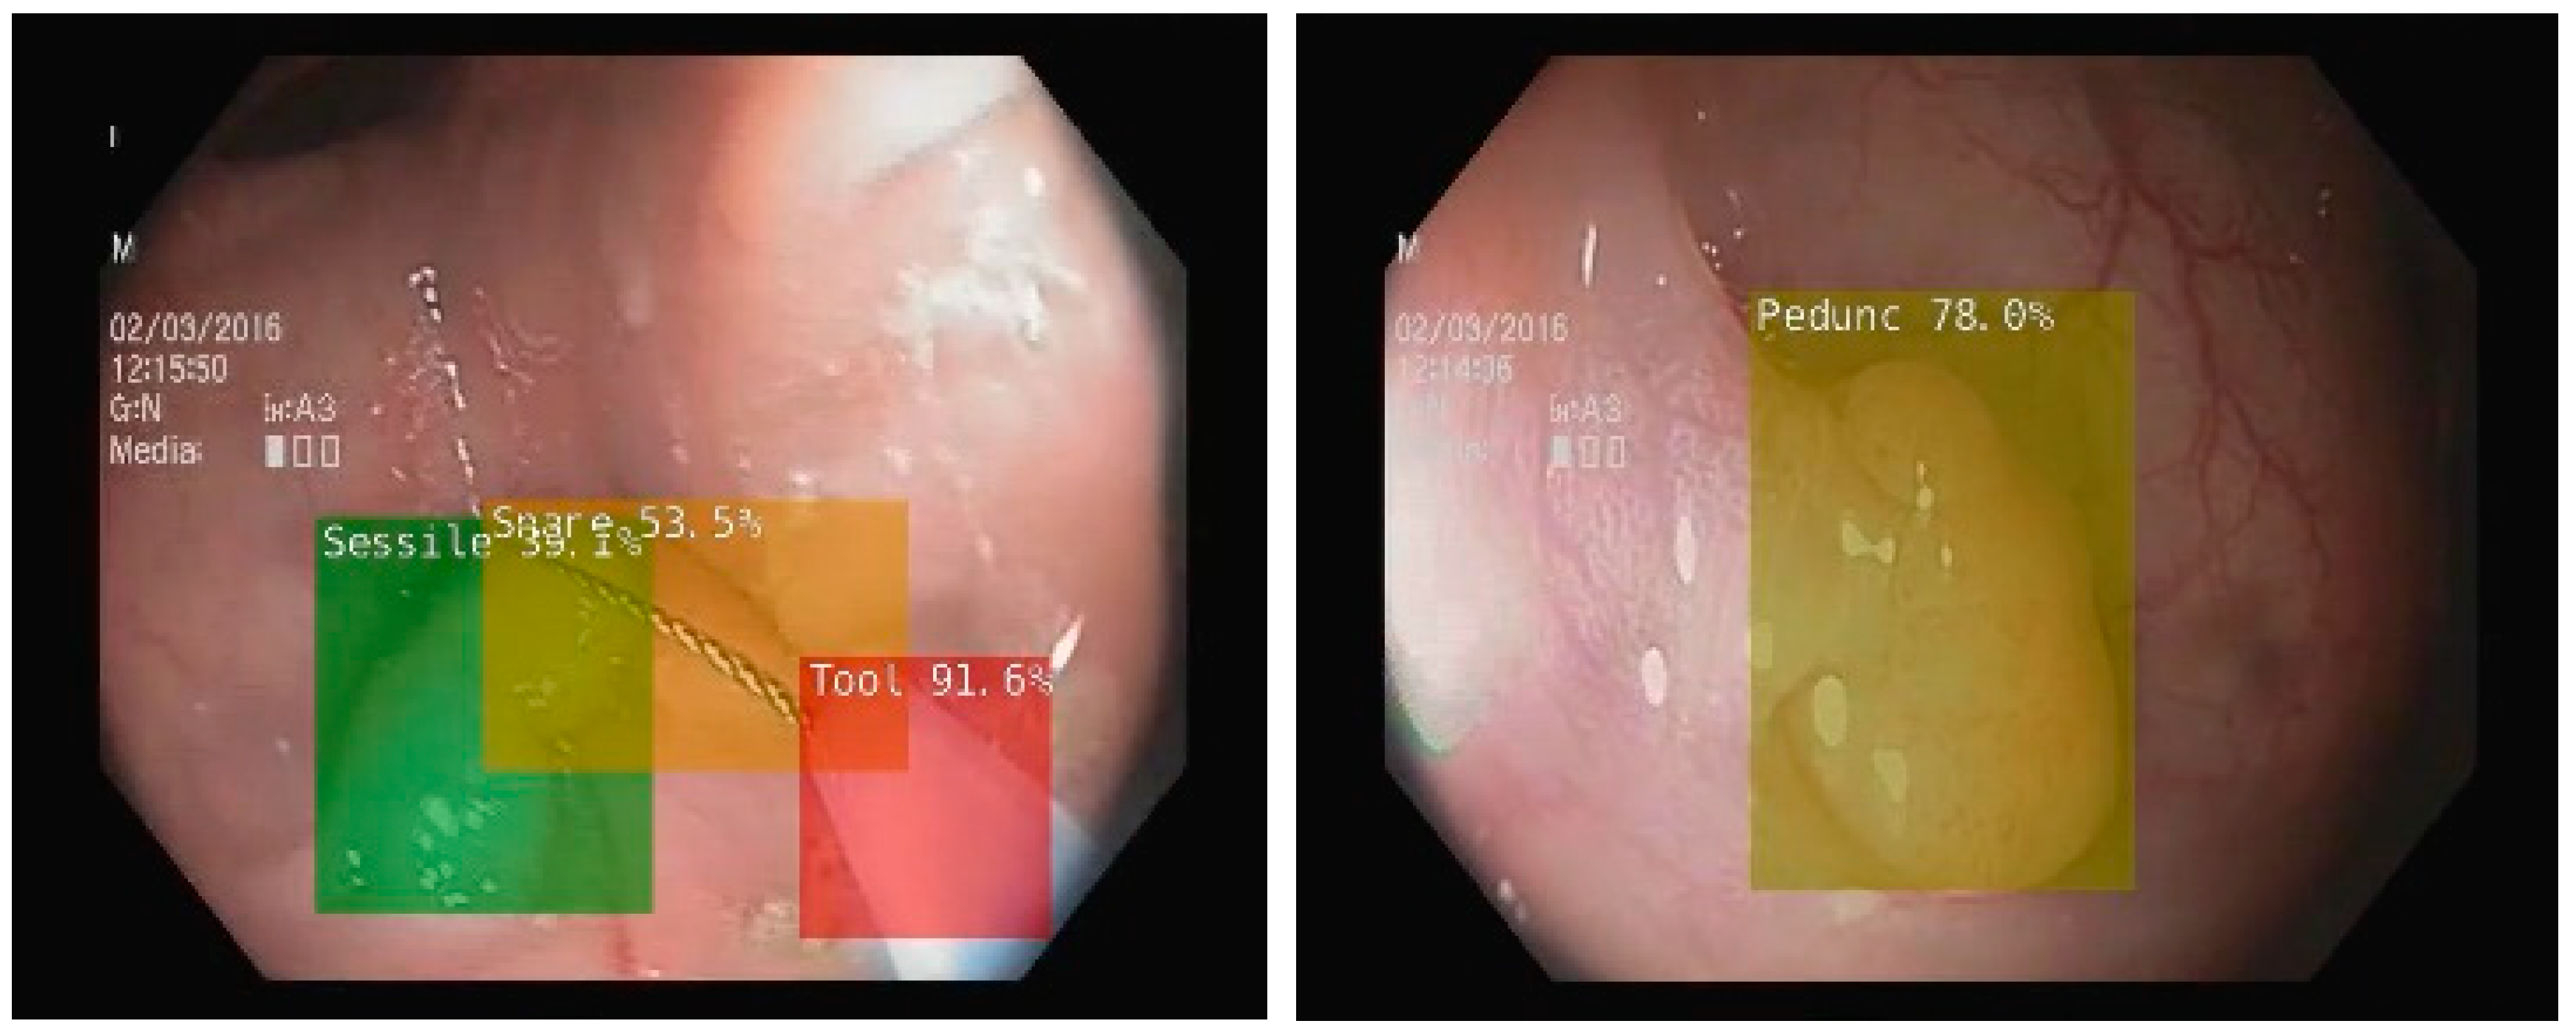

To enhance the colonoscopy examination, several other AI systems were developed and approved for use. Nonetheless, most of them were aimed at detecting and diagnosing organic lesions (Table 1) [13,23]. To achieve this, two concepts were introduced in the development of AI-enhanced colonoscopy: computer-assisted detection (CADe) and computer-assisted diagnosis (CADx). Using CADe, AI is able to assist endoscopists in colon lesion detection, thereby increasing the adenoma detection rate (ADR). We present an example from our work of developing an AI system including a CADe module, in Figure 2 [24,25]. For this system, we used MobileNet1, a deep learning network with 4.2 million parameters already trained on the ImageNet dataset, retrained for detecting several types of polyps, lesions, water jet and endoscopic instruments [26]. On the other hand, an AI system using CADx assists the investigator in distinguishing lesions and assessing their potential for malignancy [27]. For this system, the authors used an architecture based on EfficientNet, a neural network with 19 million parameters [28]. This network was also pretrained using the open ImageNet dataset. However, IBS is not associated with any organic lesions. Therefore, it is likely that the benefits of using AI technology in IBS patients will be rather indirect. If no lesions are found during the colonoscopic examination, it may be possible to improve the reliability of an IBS diagnosis by using a tool that objectively analyses the images.

Figure 2. CADe in colonoscopy on NVIDIA Jetson Xavier NX microsystem using MobileNet1 deep learning network retrained to detect more types of polyps, bleedings, water jet, and endoscopic instruments (snare, tool) [25].